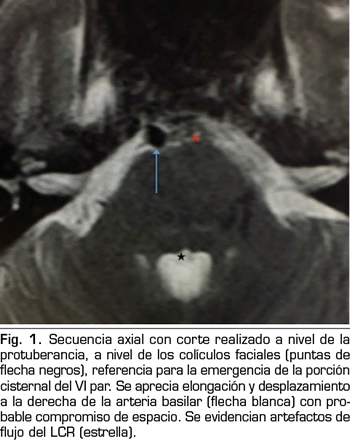

Presentamos el caso de un varón de 59 años, que cursa con un cuadro de parálisis del VI par craneal derecho, tras una cefalea postpunción dural, secundaria a una punción dural accidental durante una epidural. En la resonancia magnética, aparece un compromiso del espacio de la arteria basilar sobre la emergencia del VI par derecho. Posiblemente, esta variante anatómica vascular, lo haya predispuesto a una mayor vulnerabilidad del nervio abducens. La tracción del nervio, pudo producir una isquemia, convirtiendo a la hipotensión licuoral en el posible desencadenante de la parálisis. Con tratamiento conservador se recuperó completamente.

We present the case of a 59 years old man, who is diagnosed with a right sixth cranial nerve palsy, after the development of a dural post-puncture headache, secondary to an accidental dural puncture during an epidural. In magnetic resonance imaging, a compromise of the basilar artery space appears on the emergence of the right sixth cranial nerve. Possibly, this vascular anatomical variant, predisposed him to a greater vulnerability of the abducens nerve. The traction of the nerve could cause a neural ischemia, so intracranial hypotension could be the trigger of the palsy. He recovered completely with conservative treatment.